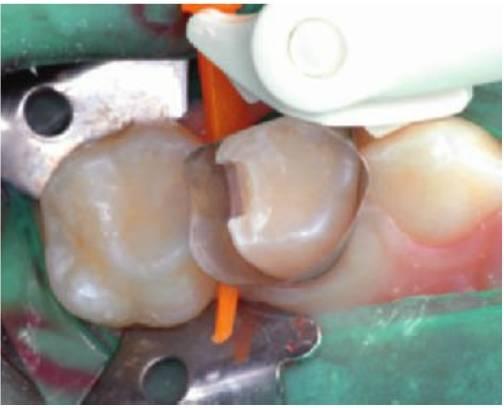

Método para realizar una restauración interproximal de amalgama (clase II)

- Utilizar anestesia local y aislamiento con dique de goma.

- Utilizar una fresa de diamante redonda pequeña o con forma de pera en una pieza de mano a alta velocidad para conseguir acceder a la caries. El contorno oclusal no debe extenderse a todas las fisuras pero sí debe incluir un pequeño istmo y una cola de milano para la retención (fig. 5.2).

- Extender la cavidad al área proximal dirigiendo la fresa suavemente hacia el gingival hasta eliminar el punto de contacto. Bucolingualmente, la cavidad debe extenderse de manera que se pueda llegar con la punta de un explorador a los márgenes de la restauración.

- Eliminar la caries más profunda con una fresa redonda a baja velocidad.

- Biselar el suelo de la cavidad en la unión entre la pared axial y el suelo oclusal para aumentar la resistencia de la restauración. Uno de los lugares de fracaso más comunes de la amalgama de clase II es el istmo, puede que debido a un volumen insuficiente de amalgama para soportar las fuerzas oclusales.

- En las lesiones profundas, colocar un recubrimiento de hidróxido de calcio o una mezcla de acetato de triamcinolona y demeclociclina, mientras que en las lesiones moderadamente profundas es apropiado colocar un recubrimiento de ionómero de vidrio fotopolimerizable sobre toda la dentina.

- Adaptar una banda matriz a la circunferencia del diente. Para llevar a cabo este procedimiento, resulta útil el uso de una banda en T curva y estrecha de bronce, especialmente si se van a colocar restauraciones adyacentes. Tanto las matrices Siqveland como las Tofflemire son adecuadas para las restauraciones unitarias, y la colocación de cuñas es fundamental para crear un buen punto de contacto.

- Insertar la amalgama de manera incremental, comenzando por la caja proximal y con el uso de un condensador pequeño para conseguir atacar bien la amalgama en todas las líneas ángulo.

- Sobreobturar ligeramente la cavidad y darle una forma curva a la superficie oclusal con el uso de un bruñidor pequeño con el extremo de bola y un recortador cleoide-discoide. Con un explorador se puede recrear la forma del reborde marginal.

- Retirar con cuidado la matriz y pasar la seda dental entre los puntos de contacto para eliminar los restos.

- Quitar el dique de goma y comprobar la oclusión.